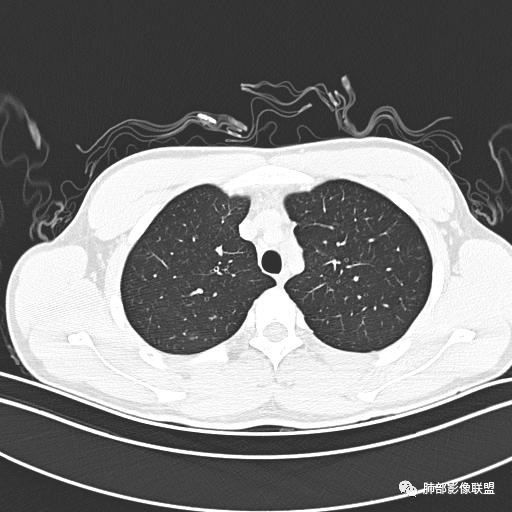

小强:青年,发热,皮疹;双肺散在结节,周围磨玻璃,点晕征,疱疹病毒感染,鉴别荚膜组织胞浆菌,结核。 大雄:青年,急性起病,发热伴全身皮疹2天,抗病毒治疗体温有下降。双肺随机分布大小不等类圆结节,“点晕征”。考虑水痘-疱疹病毒(VZV)血播询问接触史,查体皮疹分布以及形态基本可诊断。 王开金江津中心医院呼吸科:青年男性,起病急,病程短,以发热,皮疹为首发症状,感染指标以单核细胞升高为主,胸部ct双肺多发结界,周围有晕,点晕表现,随机分布,同意於老师意见,水痘疱疹病毒血流感染累及肺。 王秀仙:双肺多发大小不等结节,周围有晕,边缘模糊,呈点晕征表现。青年,急性起病,发热伴全身皮疹2天,抗病毒治疗体温有下降。考虑疱疹病毒。鉴别荚膜组织胞浆菌。 傅昌瑜:19岁男性,发热、全身皮疹2天,单核细胞增高,双肺多发结节,结节边缘见边界不清磨玻璃影。点晕征+发热、全身皮疹+单核细胞增高——考虑水痘-带状疱疹病毒肺炎。 一切∮随缘:年轻男性,发热,皮疹两天,实验室,CRP,PCT增高,影像:双肺多发散在磨玻璃结节,边界欠清,大小不等,呈点晕征改变,以血管束周围分布为主,局部血管束略增粗,其它无明显改变,考虑:1:病毒性肺炎(水痘疱疹病毒?不知道皮肤有无改变)2:真菌(组织胞浆菌,血管侵袭性肺曲霉)3:GPA4:寄生虫(实验室没有看到嗜酸细胞增高) 赵山河:双肺散在结节,周围有晕,边缘模糊,呈点晕征表现。青年,急性起病,发热伴全身皮疹2天,抗病毒治疗体温有下降。考虑水痘—疱疹病毒感染。洪桥爱:青年男性,发热、皮疹2天,伴瘙痒,皮疹于面部首发,之后进展至全身,虽然没有对皮疹进行描述,但是从出疹时间及皮疹进展情况,伴瘙痒,应该就是个水痘患者;CT提示双肺随机分布结节影,部分结节伴有边界不清晕征,考虑水痘血播肺。 刘强:年轻男性,急性起病,皮疹,发热,抗感染治疗体温下降,说明有效。影像表现为散在点晕征,感染类疾病谱(疱疹病毒,真菌,结核),结合年龄,皮肤皮疹,考虑水痘-疱疹病毒性肺炎。 小兜:男性,19岁,发热皮疹两天,颜面部至全身,CRP,降钙素及单核增高。CT示双肺散在小结节,周围伴磨玻璃影,点晕征,考虑为水痘-带状疱疹病毒(varicella-zoster virus,VZV)肺炎 必有路:青年,皮疹+发热+“点晕征”→水痘-疱疹病毒(VZV) 许慧良:青年男性患者,发热、皮疹2天,体温最高38.5℃,第3天皮疹扩展至全身,伴瘙痒,胸部CT:双肺多发随机分布的小结节,结节周边见边界模糊的晕征,考虑水痘病毒感染流心明智:男,19,急性起病,发热伴全身皮疹2天。出疹顺序头→全身,抗病毒有效。胸部CT:两肺多发大小不等类圆形实性小结节影,随机分布,结节周围环绕GGO,边界模糊,呈点晕征。出疹特点是关键,未提示。考虑:血播病毒性肺炎,水痘-疱疹病毒?麻疹?鉴别荚膜组织胞浆菌、TB、血管炎、寄生虫等。 浪迹天涯:病灶多为5-10mm大小结节,结节周围可见磨玻璃样的晕环,常多发,可分布于肺内任何区域,考虑水痘—带状疱疹病肺炎如果短时间内有新的一个区域浸润,更加能说明,